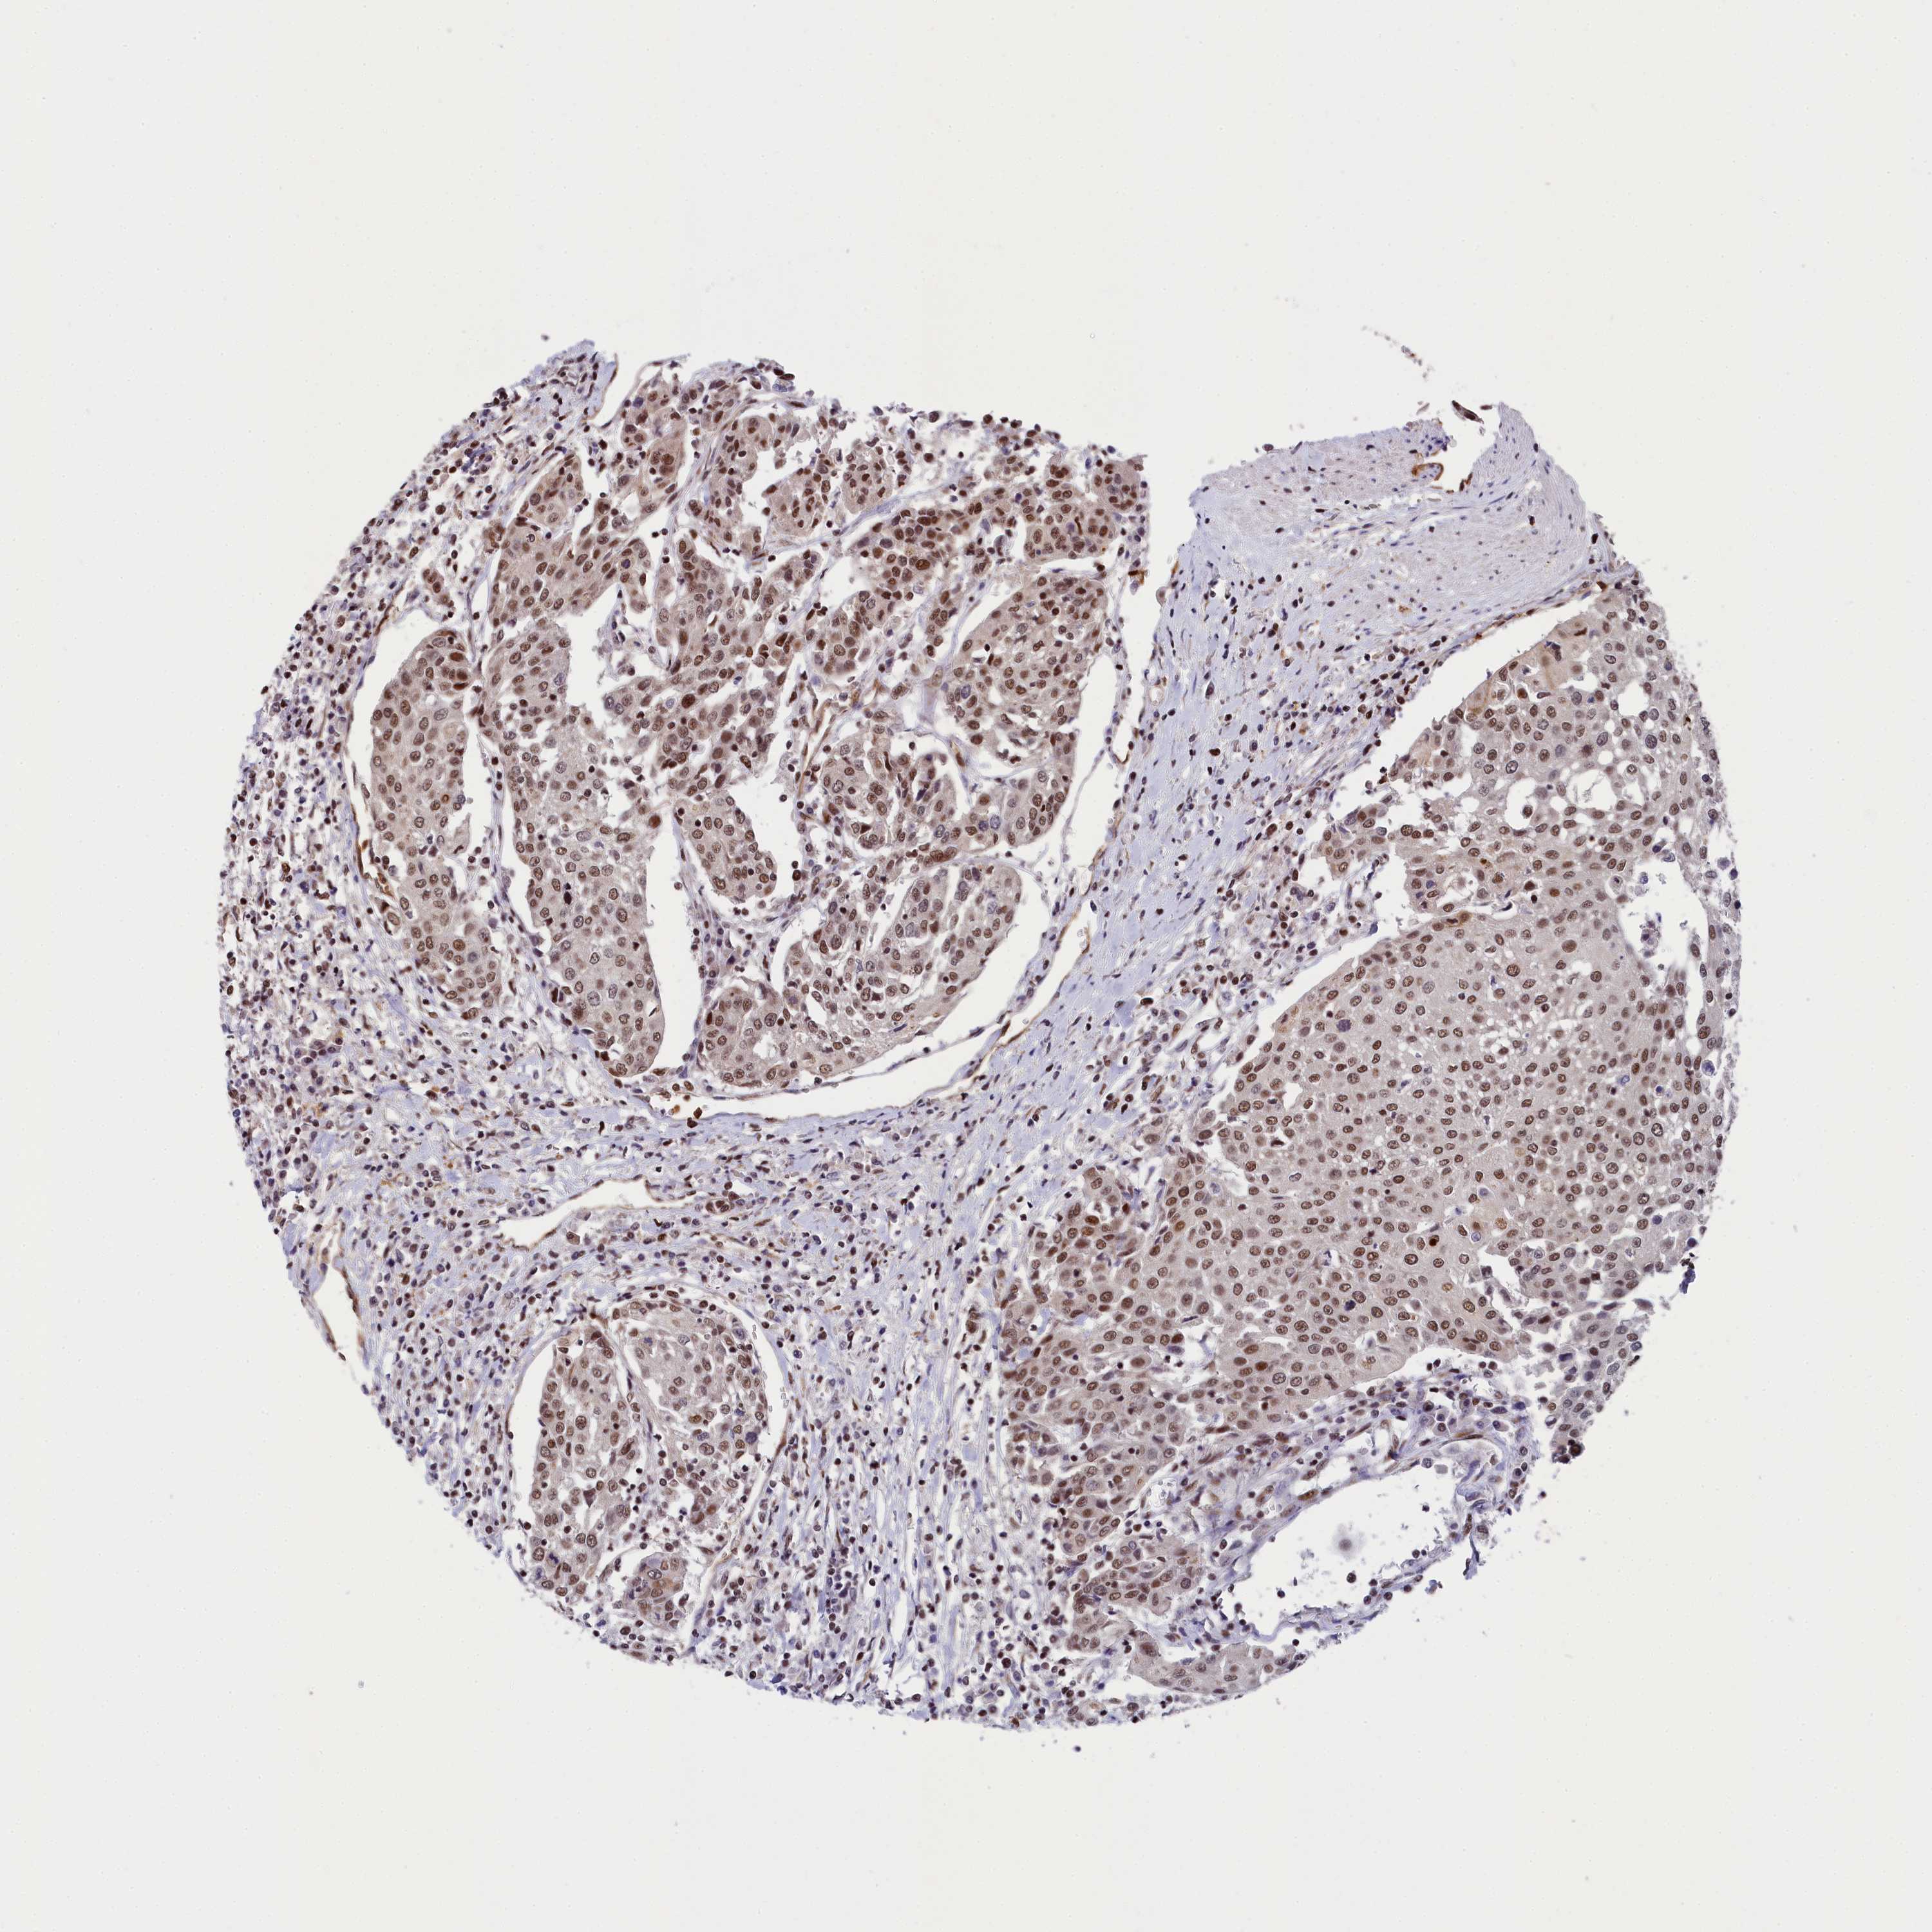

UROTHELIAL CANCER - Protein expressioni

A mouse-over function shows sample information and annotation data. Click on an image to view it in a full screen mode. Samples can be filtered based on level of antibody staining by selecting one or several of the following categories: high, medium, low and not detected. The assay and annotation is described here.

Note that samples used for immunohistochemistry by the Human Protein Atlas do not correspond to samples in the TCGA dataset.

Antibody stainingi

Antibody staining in the annotated cell types in the current human tissue is reported as not detected, low, medium, or high, based on conventional immunohistochemistry profiling in selected tissues. This score is based on the combination of the staining intensity and fraction of stained cells.

Each image is clickable and will lead to virtual microscopy that enables deeper exploration of all samples and also displays staining intensity scores, fraction scores and subcellular localization as well as patient and tissue information for each sample.

Antibody HPA041124

Staining

High

Medium

Low

Not detected

Intensity

Strong

Moderate

Weak

Negative

Quantity

>75%

75%-25%

<25%

None

Location

Nuclear

Cytoplasmic/membranous

Cytoplasmic/membranous,nuclear

Urothelial carcinoma, High grade